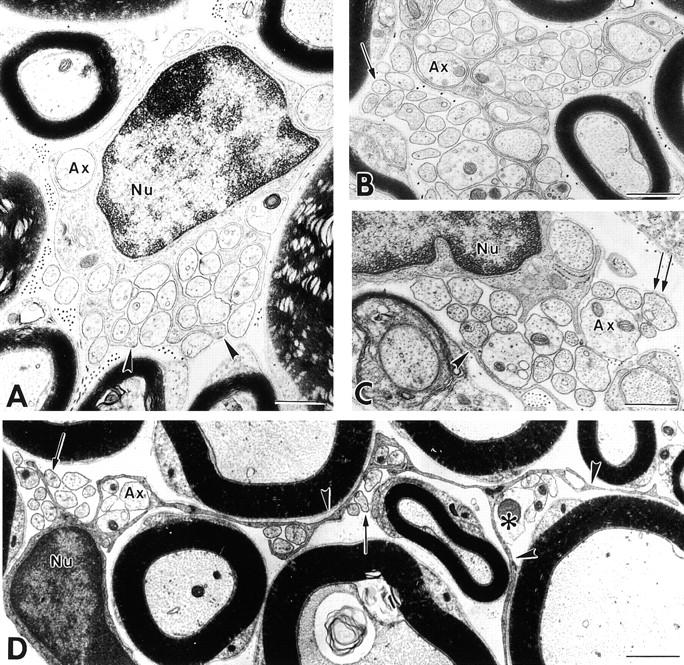

This study investigated the function of the adhesion molecule L1 in unmyelinated fibers of the peripheral nervous system (PNS) by analysis of L1- deficient mice. We demonstrate that L1 is present on axons and Schwann cells of sensory unmyelinated fibers, but only on Schwann cells of sympathetic unmyelinated fibers. In L1-deficient sensory nerves, Schwann cells formed but failed to retain normal axonal ensheathment. L1-deficient mice had reduced sensory function and loss of unmyelinated axons, while sympathetic unmyelinated axons appeared normal. In nerve transplant studies, loss of axonal-L1, but not Schwann cell-L1, reproduced the L1-deficient phenotype. These data establish that heterophilic axonal-L1 interactions mediate adhesion between unmyelinated sensory axons and Schwann cells, stabilize the polarization of Schwann cell surface membranes, and mediate a trophic effect that assures axonal survival.

本研究通过对L1基因缺陷小鼠的分析,探究了粘附分子L1在周围神经系统(PNS)无髓鞘纤维中的功能。我们证明,L1存在于感觉性无髓鞘纤维的轴突和施万细胞上,但仅存在于交感神经无髓鞘纤维的施万细胞上。在L1基因缺陷的感觉神经中,施万细胞形成,但未能保持正常的轴突包绕。L1基因缺陷小鼠的感觉功能降低,无髓鞘轴突丧失,而交感神经无髓鞘轴突外观正常。在神经移植研究中,轴突L1的缺失而非施万细胞L1的缺失再现了L1基因缺陷的表型。这些数据表明,异嗜性轴突-L1相互作用介导无髓鞘感觉轴突与施万细胞之间的粘附,稳定施万细胞表面膜的极化,并介导一种确保轴突存活的营养作用。